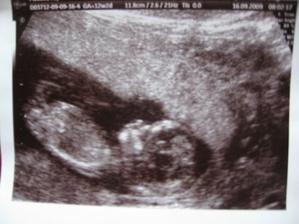

Dne 6.4. 2009 byly zavedeny dvě morulky při 1. pokusu IVF – mražáčky nezbyly žádné, ale věřila jsem, že nebudou potřeba…dne 20. 4. 2009 sdělen negativní výsledek testu. Všechno zlé je k něčemu dobré, a co tě nezabije, to tě posílí…dne 8. 7. 2009 přichází druhý pokus IVF – opět zavedeny dvě morulky a zbylo i pět mražáčků. Dne 20. 7. 2009 jsem uslyšela tu nádhernou vytouženou větu: GRATULUJI MAMINKO, JSTE TĚHOTNÁ. Dnes, tj. 4. 8. 2009, je tomu právě 15 dní, co tato věta zazněla z úst doktorky Čadové, a musím přiznat, že mám stále slzy v očích kdykoliv si na tento zázračný okamžik vzpomenu.

Vím, že ještě zdaleka nemám vyhráno, ale pevně věřím, že to s tím maličkým bobiškem uvnitř mého bříška dokážeme a dotáhneme to společně do šťastného konce.

10. 11. - ultrazvuk na prenatální diagnostice v Brně, opět potvrzeno, že náš brouček se jeví jako zdravé miminko 🙂